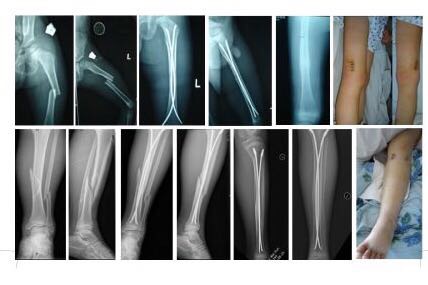

导读: 高弓足是一种常见的足部骨疾病,它对患者的影响很大。高弓足是儿童颇为常见足畸形,多为神经肌肉性疾病引起的前足固定性跖屈,从而使足纵弓增高。有时合并后足内翻畸形。偶见原因不明者,可称为特发性高弓足。